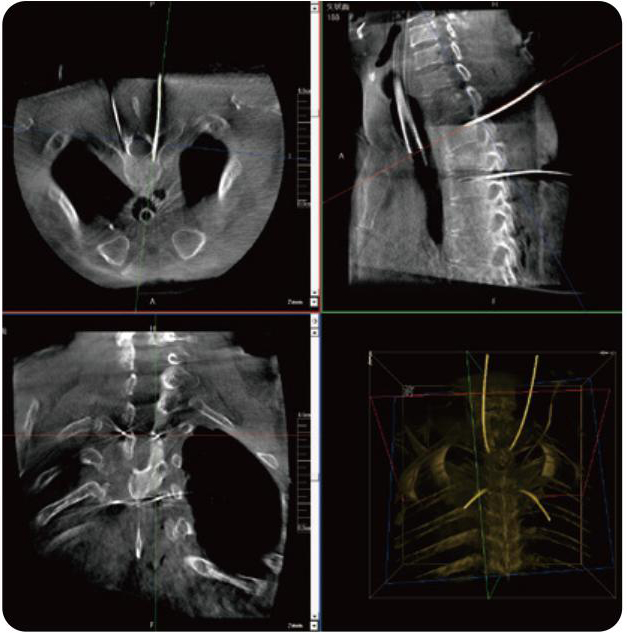

Clinical picture

临床图片